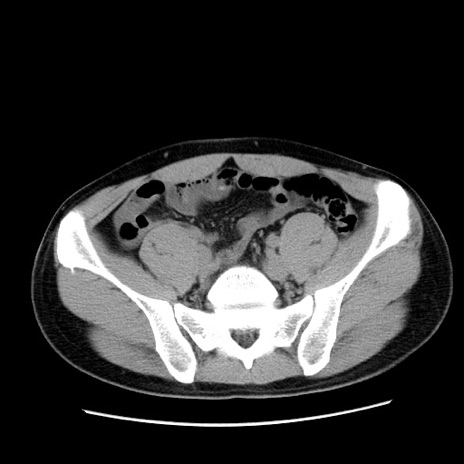

冠状断像

【症例】20歳代 男性

【主訴】心窩部痛

【現病歴】今朝より上腹部痛あり。一旦軽快していたが再度出現したため救急要請。昨日夕に白身の魚を含む刺身を食べた。

【身体所見】BP 136/89mmHg、HR 74/min、BT 37.0℃、腹部:膨満、軟、心窩部に圧痛あり。反跳痛なし、筋性防御なし、腸雑音やや亢進あり。

【データ】WBC 17700、CRP 0.48